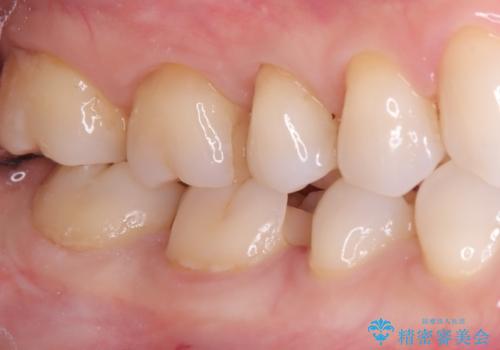

- 主訴:右下の奥歯がたまに冷たい物や甘いものでしみる

右下6番目の歯に大きめのう蝕を認め、形態の再現性を考えインレーでの治療となりました。

右下6の近心にう蝕が認められう蝕の範囲が大きかったため、歯冠形態の再現性の高いインレーでの修復とし、材質は審美性、清掃性に優れたセラミックを選択しました。